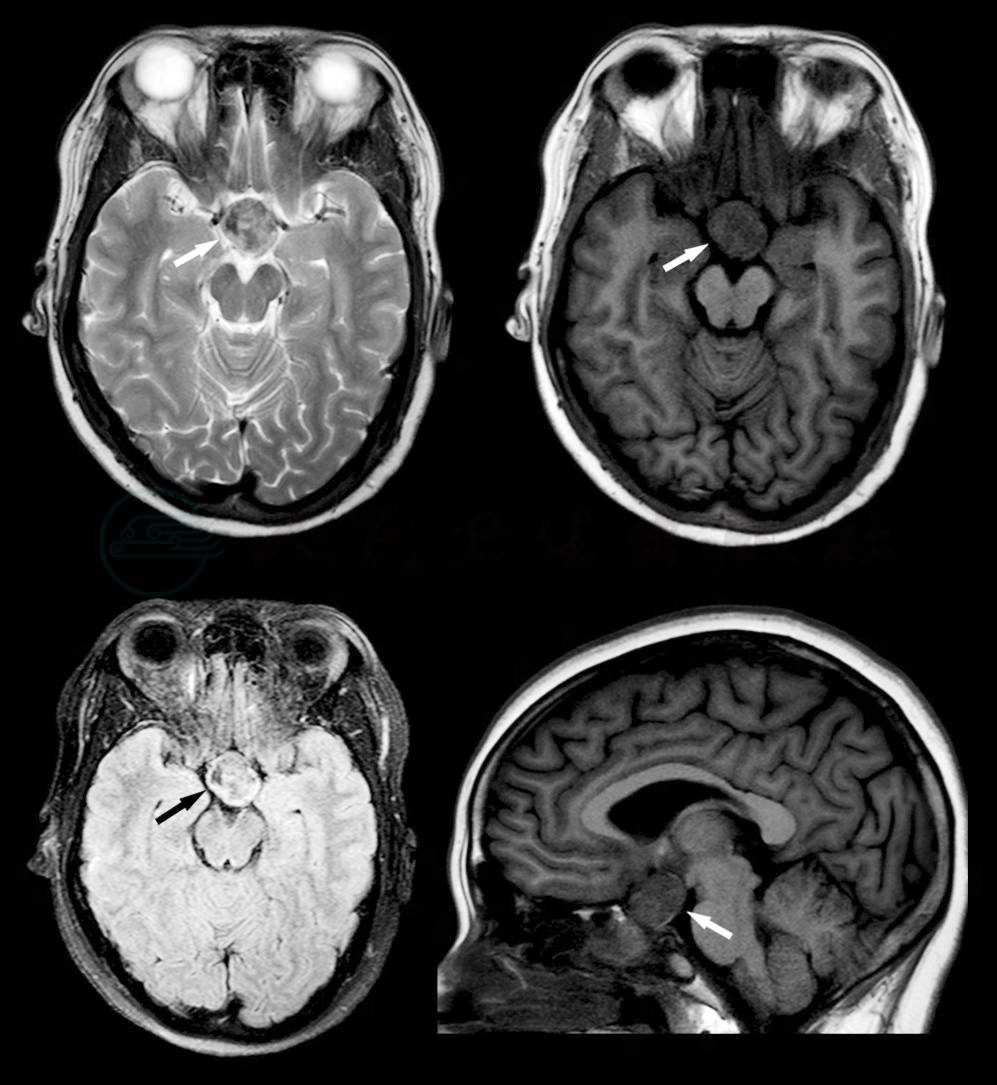

辅助检查:①三大常规、肝肾功能、电解质、甲状腺功能、乙肝、梅毒、心电图、腹部B超未见明显异常。②性激素检查:人促黄体生成素20.9mIU/ml(女性卵泡期1.2~12.7mIU/ml、排卵期15.5~90mIU/ml、黄体期0.5~14.6mIU/ml),人促卵泡生成素10.71mIU/ml(女性卵泡期 2.5~11.4mIU/ml、排卵期 3.3~21.7mIU/ml、黄体期 1.2~7mIU/ml),雌二醇 1441.34pg/ml(女性非孕期 30~400pg/ml),睾酮 0.53ng/ml(正常参考值 2.8~12ng/ml),催乳素 14.59ng/ml(女性正常参考值2.41~27.36ng/ml),孕酮0.54ng/ml(女性卵泡期0.2~2.4ng/ml、黄体期6.0~20.5ng/ml、绝经期0.1~1.8ng/ml)。③头颅MRI检查:鞍区扩大,其内见不规则形异常信号影,边界清,大小约1.6cm×2.0cm×2.2cm,信号欠均匀;双侧大脑、小脑半球对称,形态如常,脑实质未见异常信号影,脑室、脑池系统形态、大小未见异常,脑沟、脑裂未见增宽、加深征象,中线结构居中,脑干形态、信号未见异常。双侧蝶窦内见异常信号影填充。影像诊断:鞍区占位,建议增强检查(图1)。④脑电图检查:两半球基本波率为低幅不规则的快波活动,呈广泛性分布,双侧基本对称,调节、调幅差,各导联可见少量9~12Hz低幅α波,不以顶-枕区为主,混杂较多弥漫性低-中幅的θ波及θ活动。视反应未见明显改变。过度换气:未见明显改变。印象:轻度异常脑电图,轻度异常脑电地形图。⑤心理测试:韦氏成人智力测试全量表智商84,操作智商95,言语智商87;韦氏记忆测试55,测试中患者不太配合,注意力不太集中。PANSS量表阳性症状量表总分31,突出阳性症状群为幻觉、妄想;阴性症状量表总分31,突出阴性症状群为情感平淡、意志减退。

图1 鞍区占位